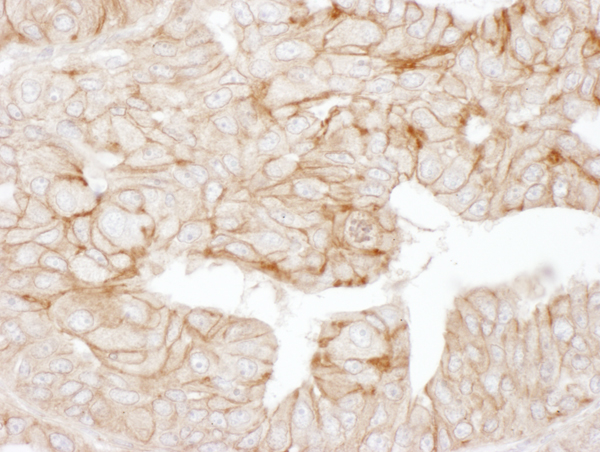

IHC (Immunohiostchemistry)

(Detection of human Alpha-Adducin by immunohistochemistry. Samples: FFPE sections of human ovarian carcinoma. Antibody: Affinity purified rabbit anti-Alpha-Adducin Cat. No. AAA212269 Lot1 used at a dilution of 1:5,000 (0.2ug/ml) (left) and Cat. No. Lot1 used at a dilution of 1:5,000 (0.2ug/ml) (right). Detection: DAB)

IHC (Immunohistochemistry)

(Detection of human Alpha-Adducin by immunohistochemistry. Sample: FFPE section of human ovarian carcinoma. Antibody: Affinity purified rabbit anti-Alpha-Adducin (Cat. No. AAA212269 Lot1) used at a dilution of 1:1,000 (1ug/ml). Detection: DAB)